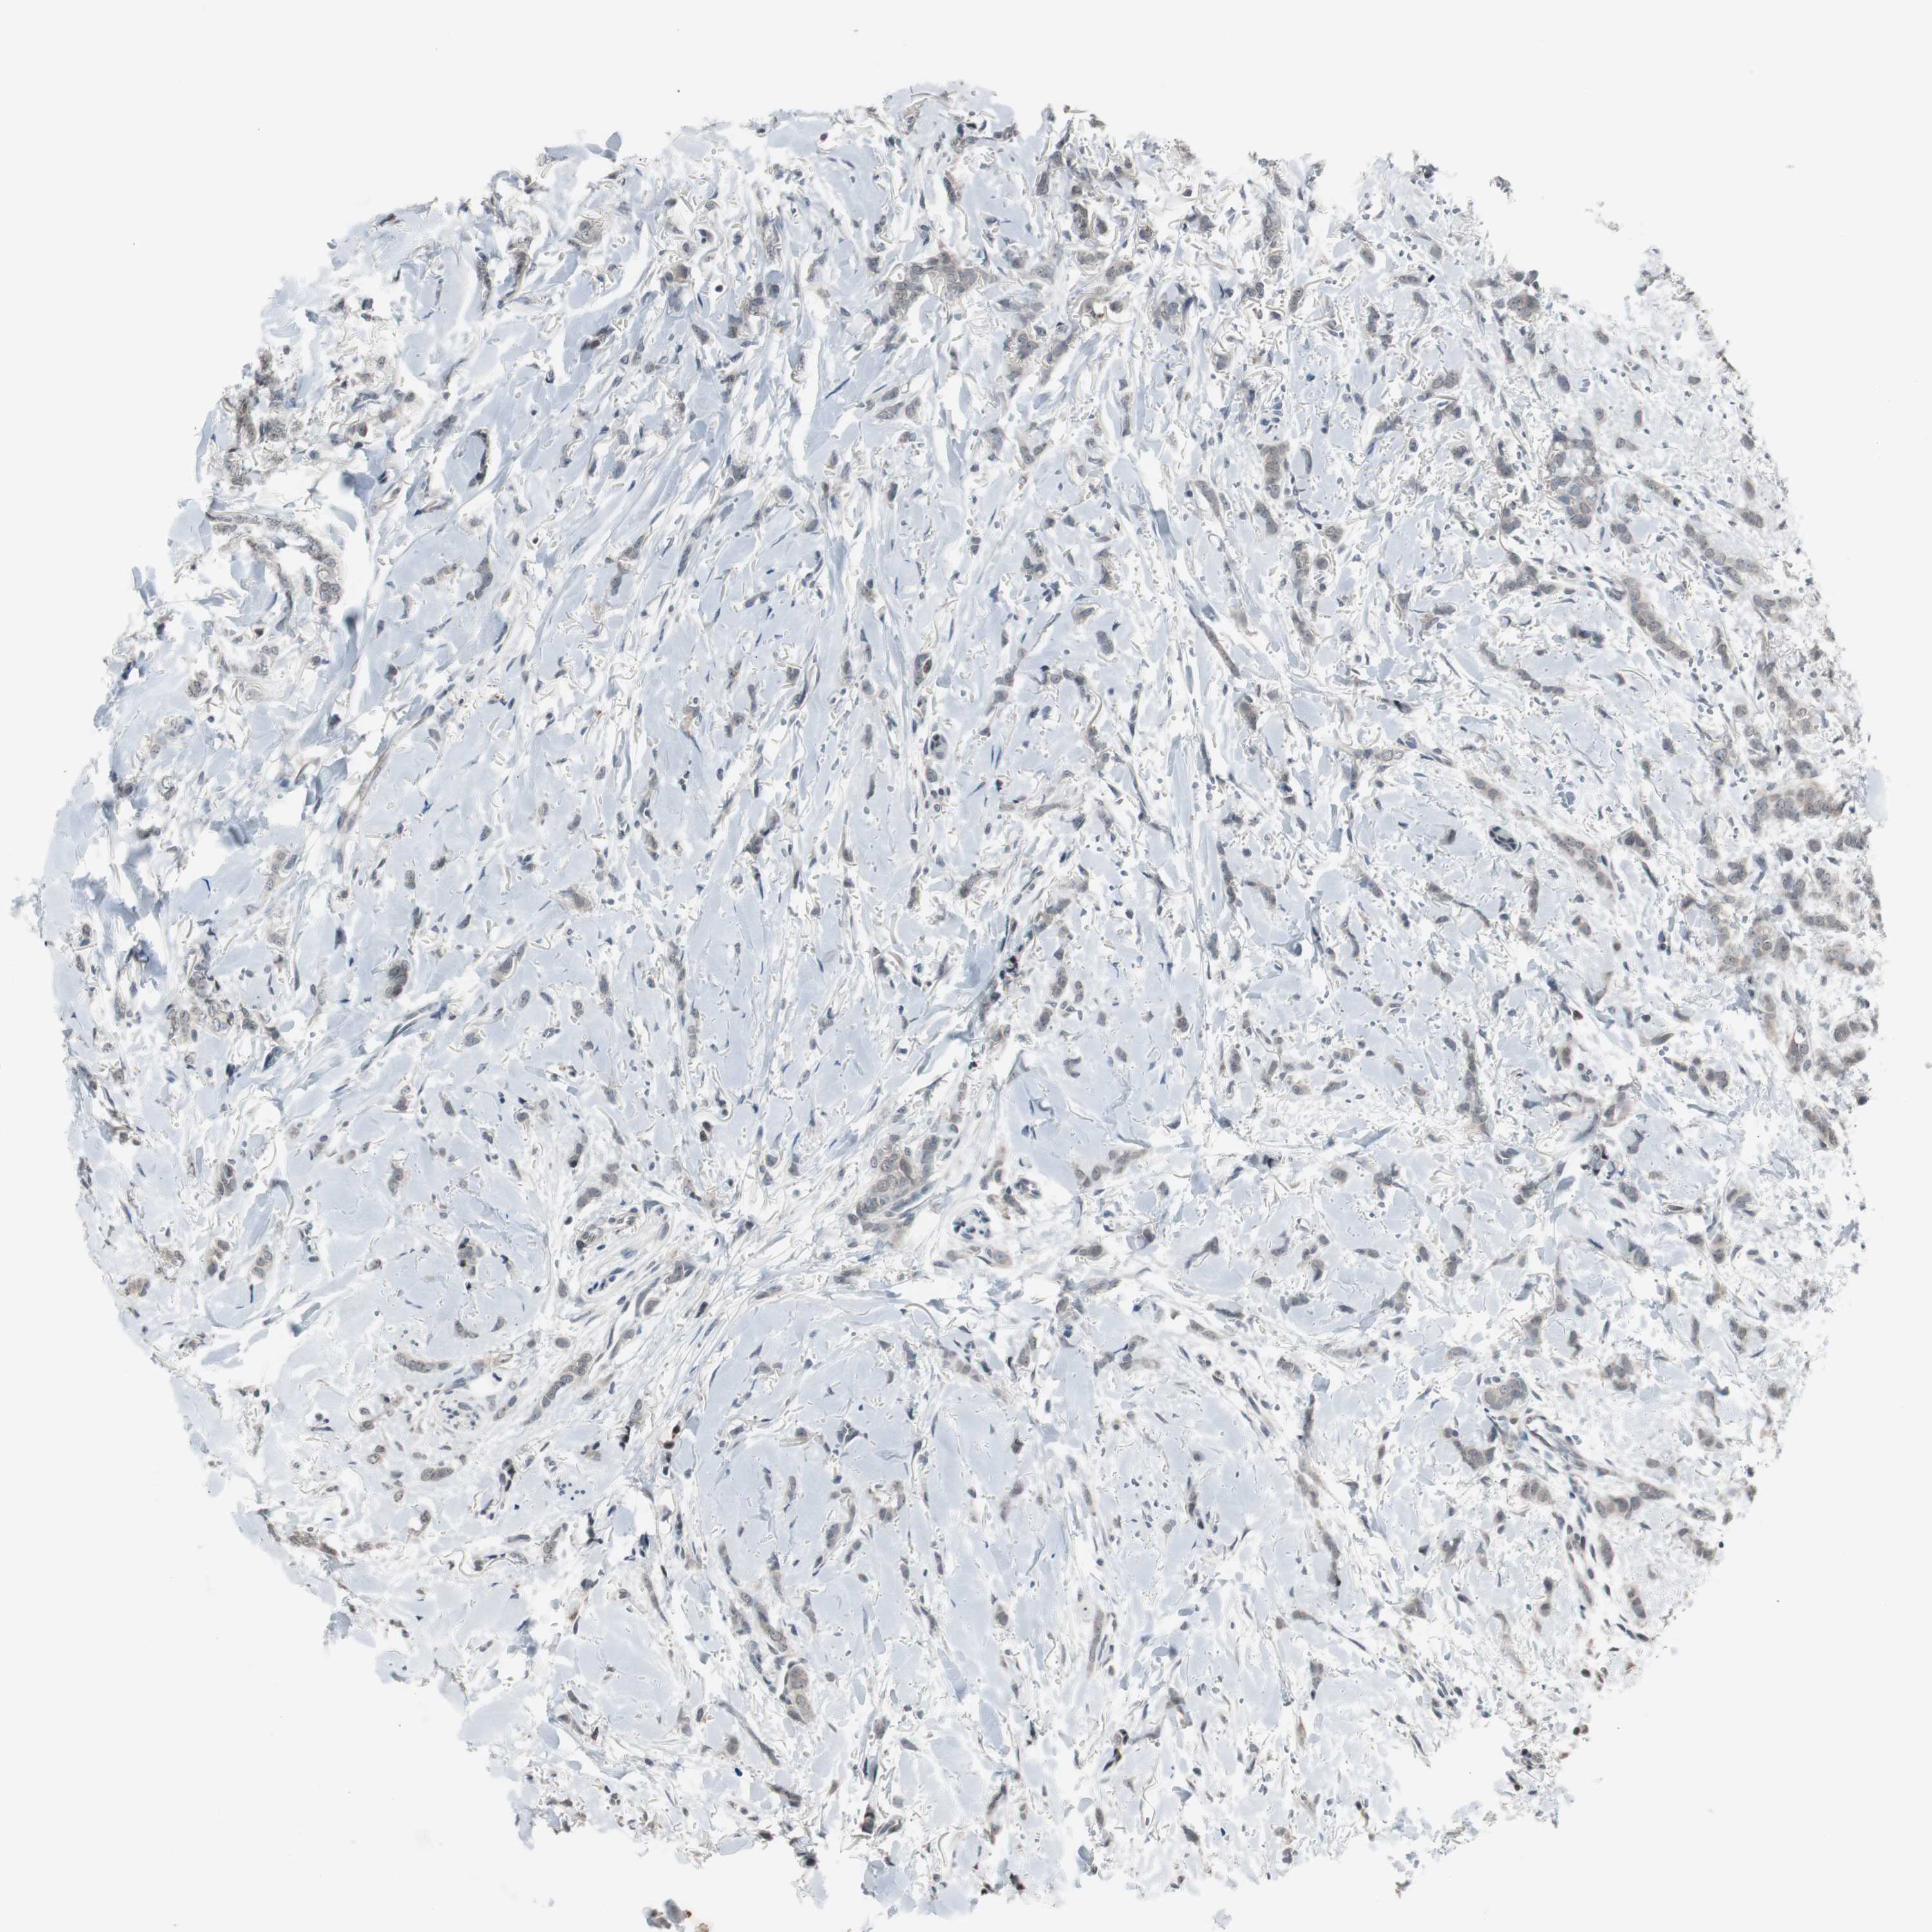

BRCA TCGA BRCA VALIDATION PROTEIN EXPRESSION

ANTIBODIES

AND

VALIDATION